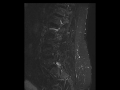

Septic Facet Arthritis

53-year-old male with recent ablation of the left L4 and L5 nerve roots for persistent back pain. There is widening of the left L5-S1 facet joint. There is loss of T1 signal within the inferior articular process of L5 on the left and superior articular process of S1 on the left. Marrow edema and an effusion centered at the L5-S1 facet are demonstrated on the STIR image. On the post contrast axial T1-weighted image, there is a thick rind of peripheral post contrast enhancement. The findings are compatible with septic arthritis of the left L5-S1 facet joint. Hematogenous infection of the facet joints is rare. Iatrogenic cases are much more common. MRI is an excellent exam of choice as it can better assess spread of infection to the spinal canal and paravertebral regions.